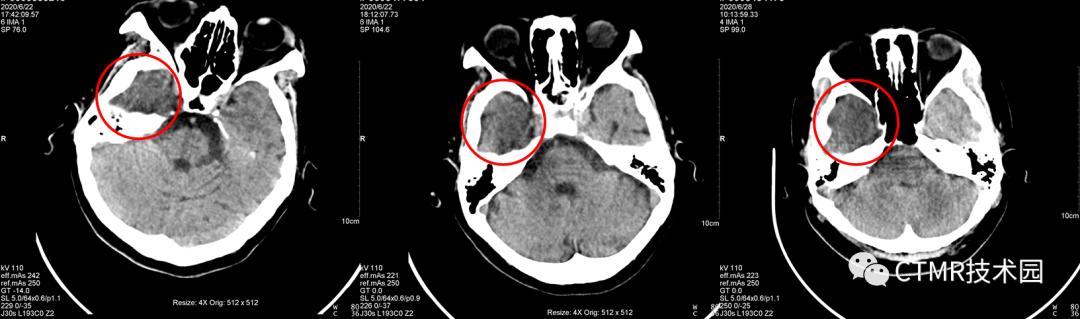

上周我在此机器值班,因为此伪影一直在我脑子里存留,平时在上 Philips Brilliance 64 CT 时,注意观察了下它扫描颅脑的螺距,非常小,可供选择的范围很小,最大可选 0.399。飞利浦的机器比较好的一点就是,它固化了 Scan type,不同的扫描部位/检查方法定义不同的 Scan type,那么在 Brain 扫描类型下,再进一步限制 Collimitation,螺距,Rotation time 等一系列参数,以期获得最佳的的图像质量。那么我就在此机器上尝试选用小螺旋扫描,最小可以改到 0.35,扫了几个病人,伪影完全消失!可以证明,在西门子这台机器上采用大螺距扫描是不合理的,应当也使用小螺距扫描。而且采用小螺距 DLP 还降低了,那么可以进一步增大 QRM,以期获得更好的图像。

那么如何去除呢?就需要减小螺距,减小到什么程度呢?产生伪影的暗区在 z 轴范围上的距离小于等于螺距乘以探测器宽度的距离。从图像上观察,这个暗区的范围大概是 2~3 层,那么就是 1cm ~ 1.5cm 的范围,那么再结合探测器宽度 64*0.6mm = 3.84cm,那么为了保障预留足够的范围,螺距应当设在稍微比 0.5 大些,那么可以设置 0.5 或 0.55,当然更小的螺距也是可以的,但结合整体扫描时间,还是尽量在没有伪影范围内适当大些。

为什么要这么设置螺距呢?为的就是让球管从伪影侧再曝光一次,以弥补射线硬化而产生的伪影。这样重建出来的图像就会削减本文一开始所说的伪影。

问题1:为什么都是经常出现在右侧呢?因为颅脑大致头足范围都差不多,且都是从头向足螺旋扫描,那么螺旋扫描时可能恰好采集伪影区域层块时,是从头左侧先转的一整圈,那么就导致了右侧不在一个完整的环上,因为转过来时已经跑到下一层块了。其实有时病人以 1.1 螺距扫描是没有伪影的,比如头颅扫描范围有所偏差时,那么上一圈扫描结束位置恰好在前 A 位置,那么伪影这一层块扫描时时恰好左侧与右侧颞部基本都在一整圈范围内。这样的情况也是会出现的,那么此时图像上右侧就不会出现明显的暗区伪影。为了验证如此,我还将扫描顺序更改了下,按足向头扫描(如下图),恰恰暗区伪影经常出现在左侧。当然球管到底是怎么转的,如果能够打开机架外壳,仔细看看就好了。